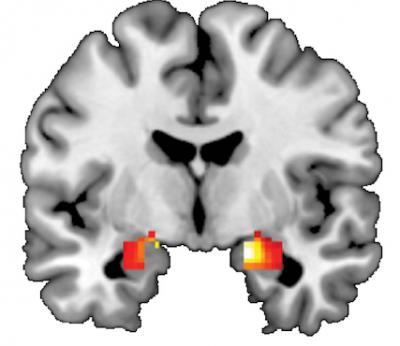

"Varying the DNA sequence in this gene has been shown to predict activation in the amygdala and is linked with depression, so we were interested in determining if DNA methylation may be playing a role in regulating how the brain responds to stress, ultimately making an individual vulnerable to stress-related disorders like depression," Dr. Williamson said. The amygdala is a region in the temporal lobe of the brain that helps shape behavioral and biological responses to threat and stress.

Initially, the team performed imaging of the brains of 80 participants in a study of Duke undergraduates led by Dr. Hariri. Students were shown angry or fearful faces and researchers recorded their responses in the amygdala. Working with Karestan Koenen, Ph.D., at Columbia University, the team also measured the amount of methylation on serotonin transporter DNA from the participants' saliva.

To extend and replicate the initial findings, the team examined brain images and DNA in 96 adolescents ages 12 to 15 participating in the Teen Alcohol Outcomes Study (TAOS), a different long-term study led by Dr. Williamson. Researchers again measured amygdala reactivity to angry or fearful faces as well as methylation of the serotonin transporter gene this time in participants' blood. The analyses revealed an even stronger link between methylation and amygdala reactivity.

To determine if their findings were occurring directly in the amygdala, the group then collaborated with Etienne Sibille, Ph.D., at the University Pittsburgh, to analyze DNA methylation patterns and gene expression in the brains of people who had passed away. To the group's surprise, they received the exact same results. "The methylation sites on the fMRI images corresponded perfectly with lower levels of the serotonin transporter expression in the amygdala. Methylation was suppressing the expression of the gene," he said.